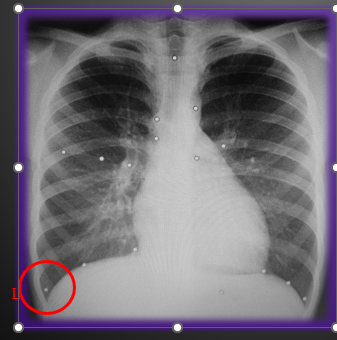

<p>¿Qué estudio es?</p>

¿Qué estudio es?

Radiografía simple